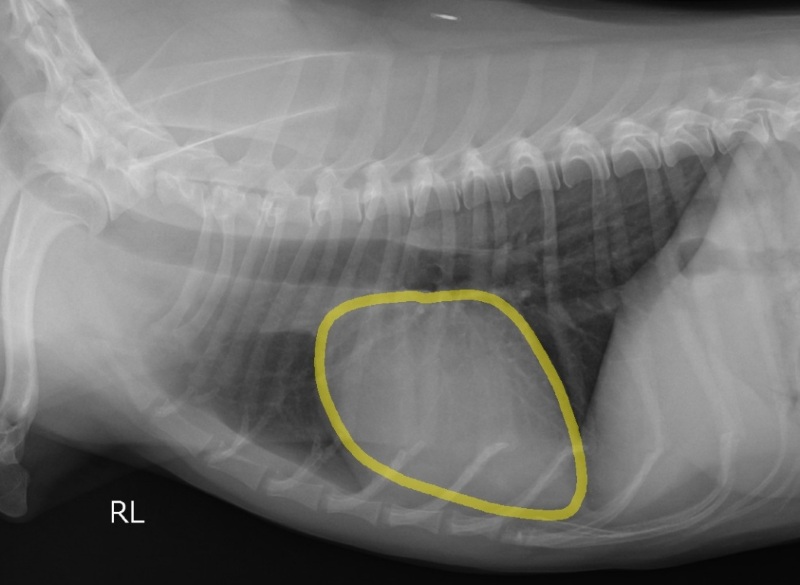

逆流によって心臓内で血液が渋滞し、初期では運動不耐性が認められます。進行すると渋滞した血液によって心臓が大きくなり、気管を圧迫して咳が出やすくなります。さらに進行すると、血液が肺から心臓に進めなくなり、肺の中に血液があふれて溺れたような状態に陥ります。これを心原性肺水腫と呼び、命にかかわります。

ステージB2:僧帽弁逆流があり、心拡大がみられる